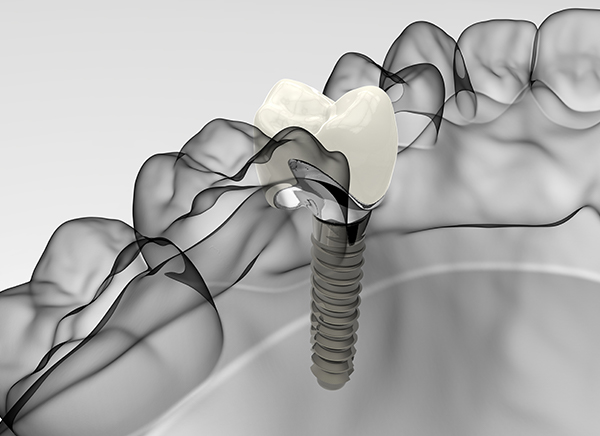

单颗/多颗种植

Single multiple

implant -

智能种植

Intelligent

implant -